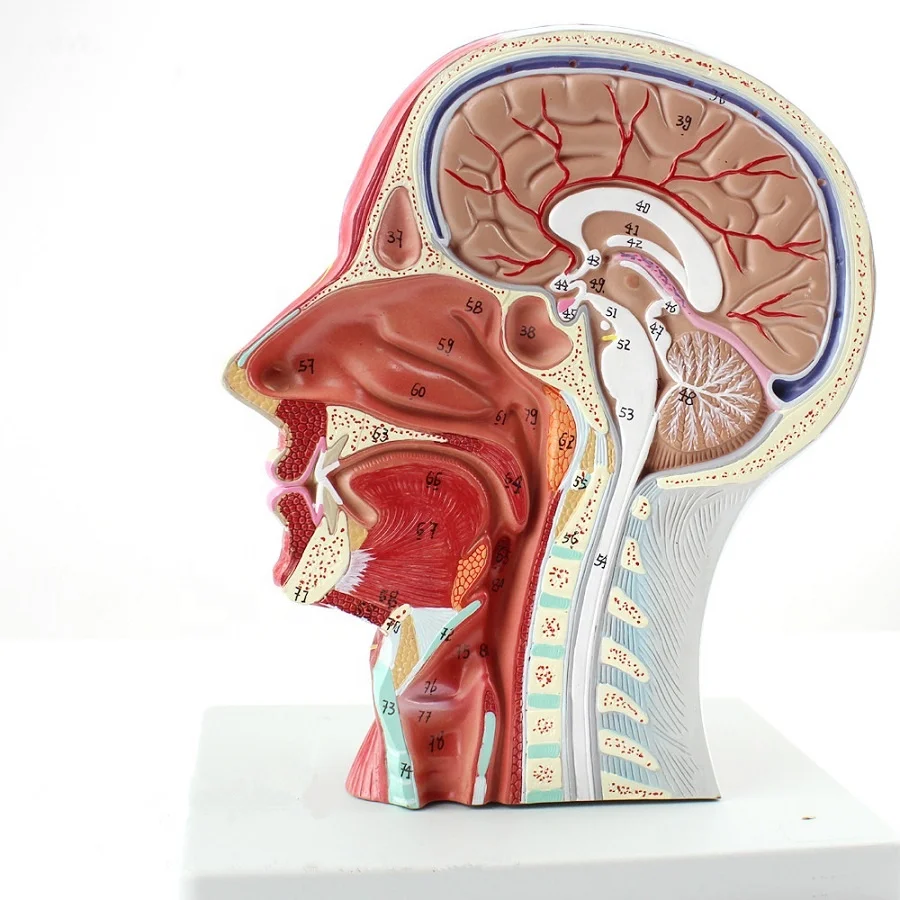

1. The double sided model shows median sagittal sectioned head anatomy, displaying brain, nasal cavity, oral ccvity and pharynx cavity.

2. Anatomically mimic muscular system with the main superficial arteries, veins and nerves and the area of the neck are demonstrated.

3. 100 positions are displayed.

Size:life size 27*10*20cm